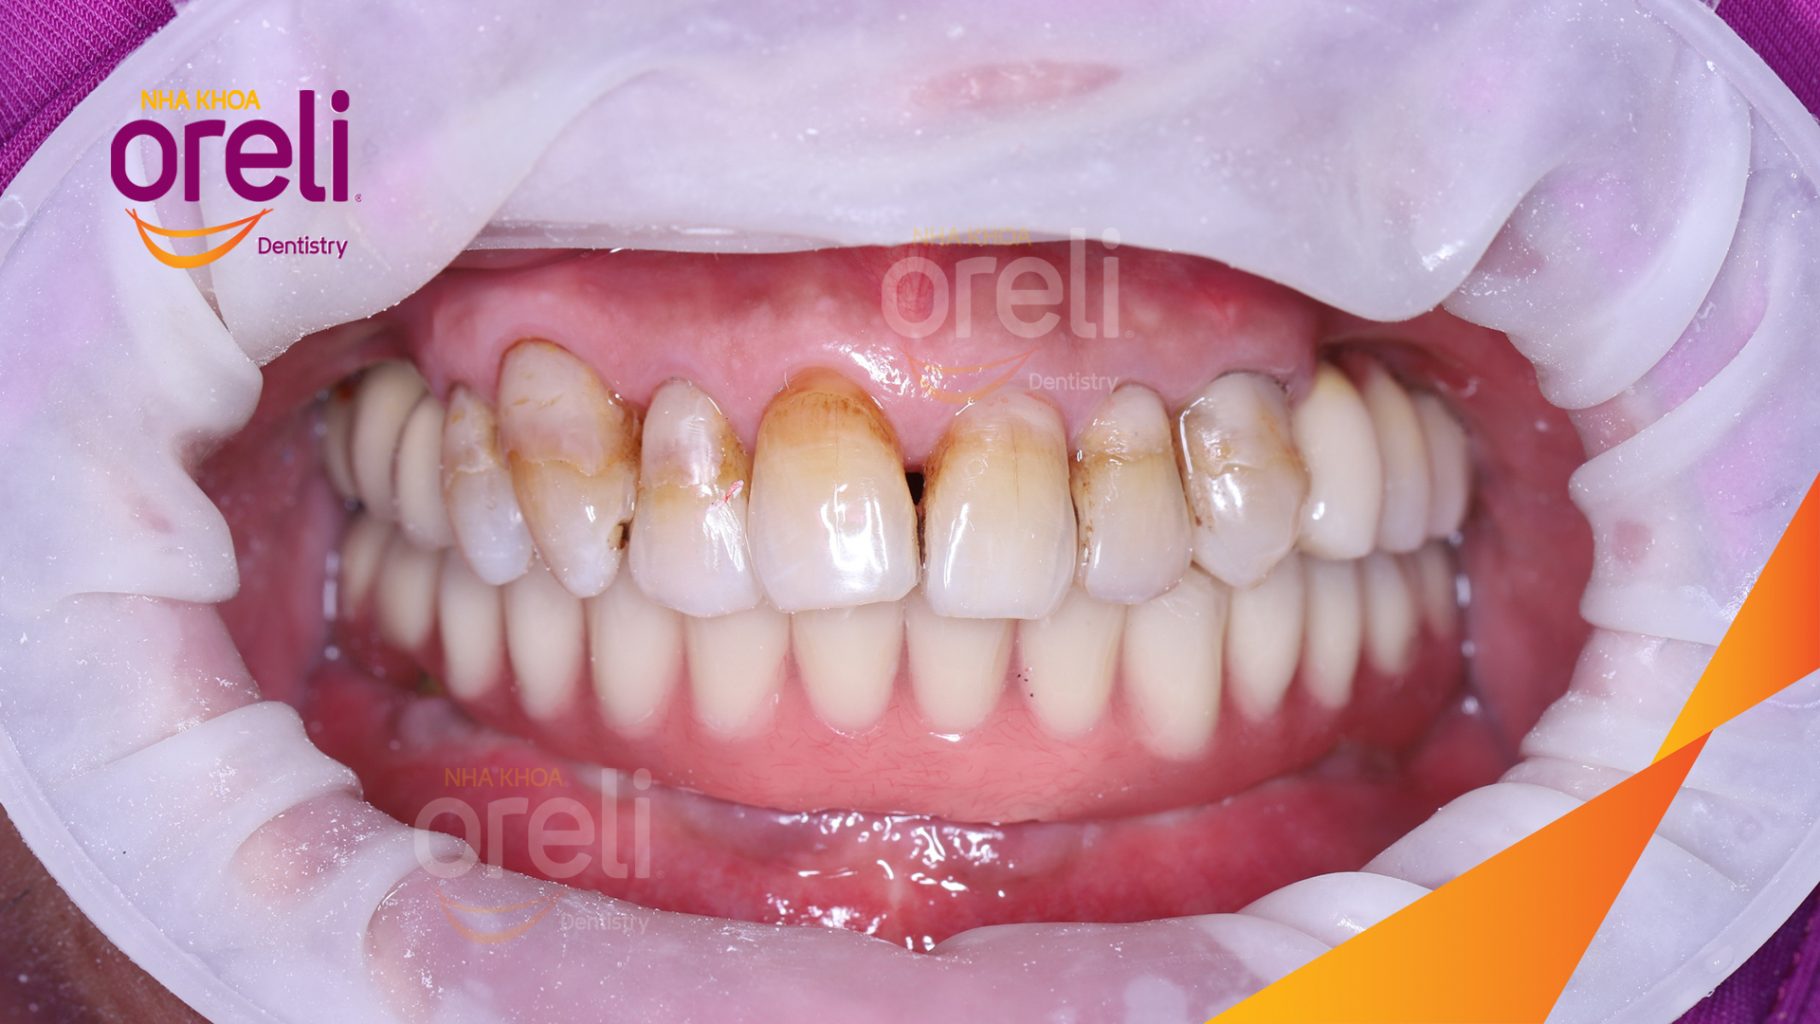

Tình trạng: Mất răng nhai vùng hàm trên và dưới

Giải pháp: Trồng răng implant toàn hàm dưới và vùng răng sau hàm trên

Kết quả: Ăn nhai tốt và thoải mái trong miệng

Hình ảnh thực tế